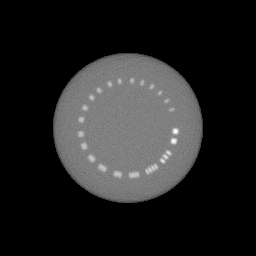

The spatial resolution of the reconstruction was measured with the Monte Carlo imaging of the CTP528 phantom [53], which includes a high-resolution test gauge ranging from 1 to 21 line pairs per centimeter embedded within a uniform material. By minimizing the presence of high-contrast materials and utilizing a radial design, the CTP528 module effectively reduces streaking artifacts. The inserts are arranged in a circular configuration, specifically designed to facilitate the evaluation of spatial resolution through Modulation Transfer Function (MTF) analysis.

3.4 Evaluation of the CTP528 Phantom

Spatial resolution is a critical parameter in evaluating the performance of an image reconstruction algorithm. It refers to the ability of the imaging system to distinguish between small structures in the object being imaged. In essence, it measures the contrast between adjacent features—higher contrast implies that smaller structures can be differentiated effectively. Typically, spatial resolution is quantified using metrics such as line pairs per millimeter (lp/mm) or line pairs per centimeter (lp/cm), where a higher number of line pairs indicates a better resolution [49, 20].

In any imaging system, the inherent effect is similar to a blurring of the image, where fine details become smeared out. This blurring can be mathematically characterized by the Point Spread Function (PSF), which describes how a single point in the object space is distributed in the image space. The PSF essentially encapsulates the extent of the blurring effect introduced by the imaging system.

To analyze the frequency behavior of the system, the Fourier transform of the PSF is computed, resulting in the Modulation Transfer Function (MTF). The MTF provides a comprehensive description of how different spatial frequencies (i.e., the rate of change of intensity in the image) are transferred by the imaging system. High spatial frequencies correspond to finer details in the image, and a higher MTF value at these frequencies indicates that the system can accurately reproduce those details.

The spatial resolution is commonly defined by the point on the MTF curve where the MTF value drops to 10% of its maximum. This MTF(10%) value represents the spatial frequency beyond which the imaging system’s ability to differentiate between structures diminishes significantly, serving as a standard benchmark for comparing the resolution of different imaging systems or reconstruction algorithms. This method to acquire the MTF(10%) values was motivated by [51], however we note that various evaluation methods may provide slightly different spatial resolution values.

For the evaluation of the reconstructed image of the CTP528 phantom, an automatized strategy has been developed based on [51] and [41]. The main steps of the evaluation follows as:

-

(i)

The reconstructed RSP matrix is rotated such that the Region of Interest (ROI) consistently appears in the same position. The rotation angles of the inserts are specified in the GATE macro of the phantom.

(ii)

The ROI is extracted, and line profiles are recorded along several projections to reduce uncertainties (see Figure 5).

Figure 5: Extracting the RSP profile along a line of the Region of Interest at the 1 lp/cm region of CTP528 phantom. -

(iii)

The local minimum and maximum values of the line profiles are determined and subsequently averaged (see Figure 6 as an illustration).

(a)

(b) Figure 6: The intensity profiles and the found minima/maxima for the 1 lp/cm segment of the reconstructed CTP528 phantom. -

(iv)

The contrast is computed from all minimum and maximum pairings as:

(15) -

(v)

The MTF is calculated for all investigated insert sizes as the following:

(16) where is taken as the contrast between the ground truth RSP values of aluminum and water.

(vi)

Finally, a parametrized sinc function is fitted to the contrast values in order to mitigate the uncertainty, and the 10% threshold is extracted from the resulting fit as the spatial resolution of the image reconstruction system.

The result of the reconstructed images of the CTP404 and CTP528 phantoms are shown in Figure 8, on the top and bottom rows respectively. The left-hand side column of Figure 8 presents the idealized case, while the middle and right-hand side columns show the more realistic silicon pixel and silicon strip detector models, respectively.

After processing 43 million protons, the spatial resolution was found to be 4.88 lp/cm for the ideal setup, 3.11 lp/cm and 2.33 lp/cm for the silicon pixel and the silicon strip detector based setups, respectively. As it is visible also on the middle and right panels of Figure 8, the detector uncertainties result in a more blurred final image.

Our reconstruction for the CTP528 phantom shows that 4.88 lp/cm, 3.11 lp/cm and 2.33 lp/cm resolution can be achieved for the ideal, pixel and strip detector models respectively. With this, we were able to achieve the 97% of the limiting Nyquist frequency for the 1 mm/px resolution for the ideal case, while 62% and 47% for the pixel and strip detector models respectively.